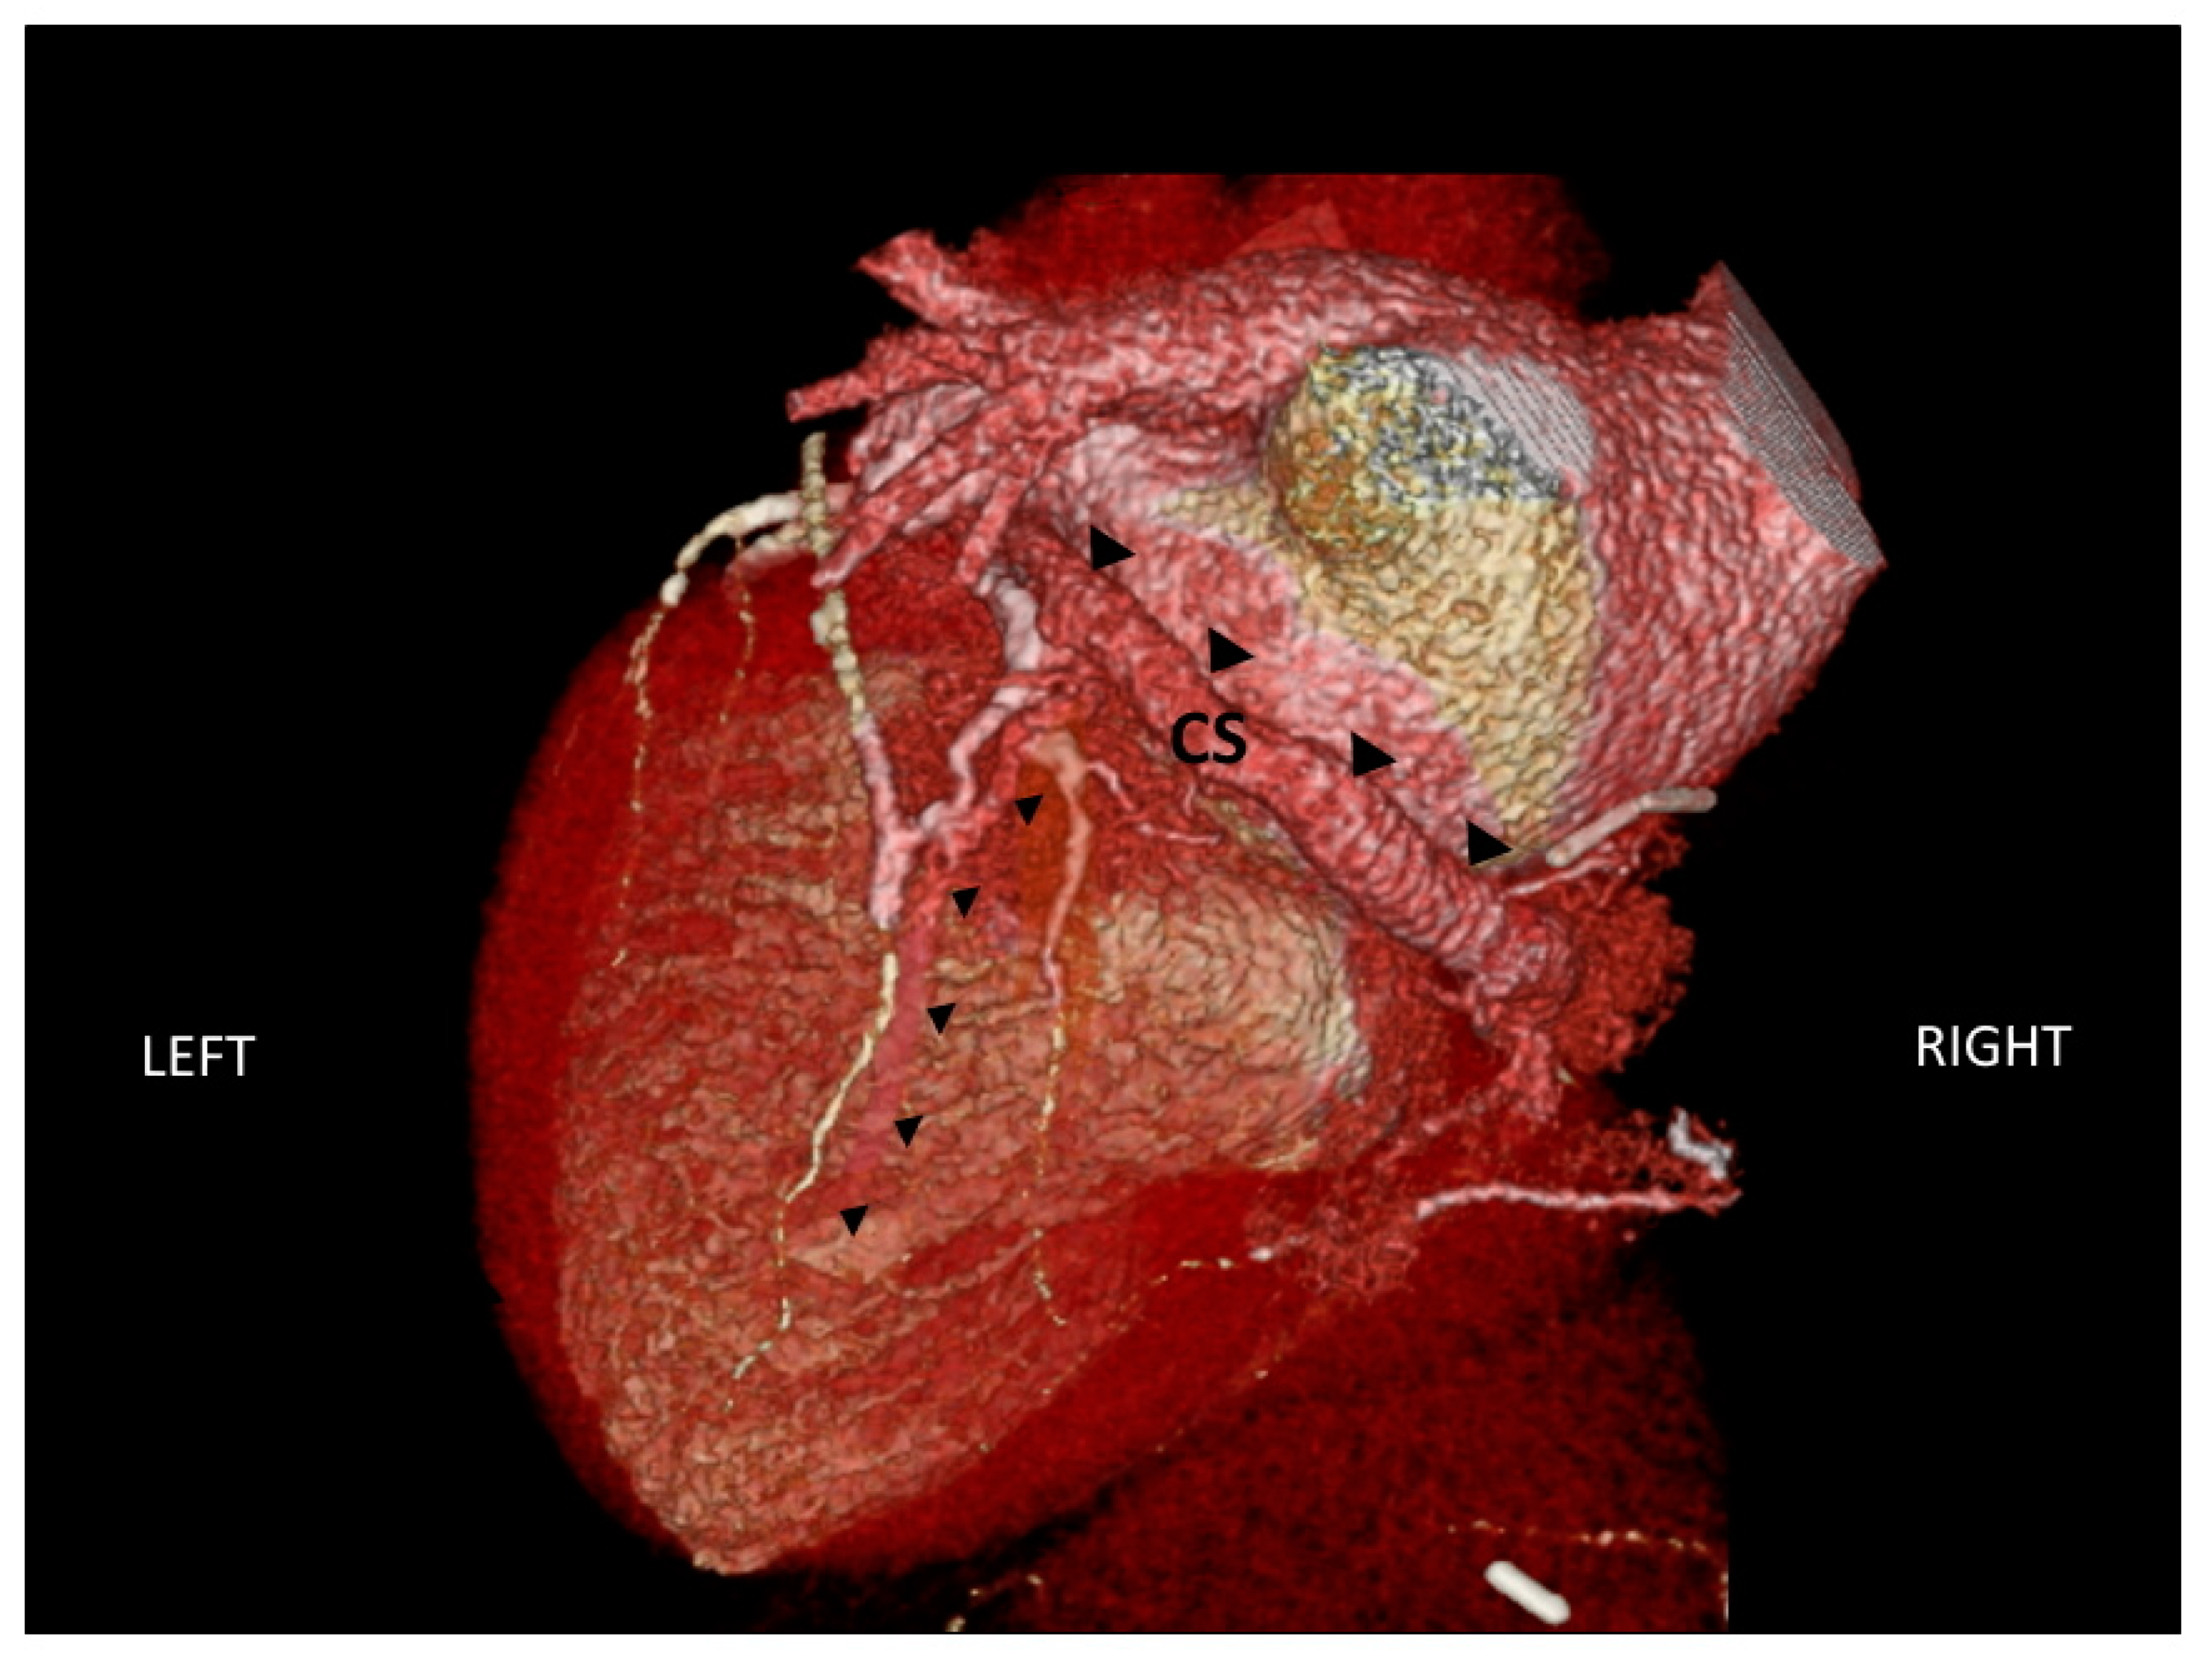

Before CRT implantation, it may be useful to have detailed information on cardiac venous anatomy to guide LV lead positioning. The anatomic characteristics of the coronary sinus system may indeed hamper the access to coronary sinus tributary veins. Multi-slice CT can be used to assess cardiac venous anatomy (Figure 5), as well as LV volumes and LVEF [32]. In the study by Girsky et al. [33], a pre-procedural review of coronary venous anatomy, assessed by cardiovascular CT, was associated with decreased implantation times and the utilization of contrast, fluoroscopy, and guide catheters.

Figure 5.

CT scan of the anatomic characteristics of the coronary sinus (indicated by large black triangles) and one of the tributary veins (indicated by small black triangles). CS: coronary sinus.

In a recent pilot study [34], a combined imaging approach, based on the assessment of coronary venous anatomy, in contrast to CT venography and myocardial viability by myocardial perfusion imaging, showed promising results for the identification of the optimal LV pacing site. Despite these results, anatomic constraints may often require using less favourable coronary venous sites during CRT implantation, and this may be responsible for a portion of non-responders observed in clinical practice.